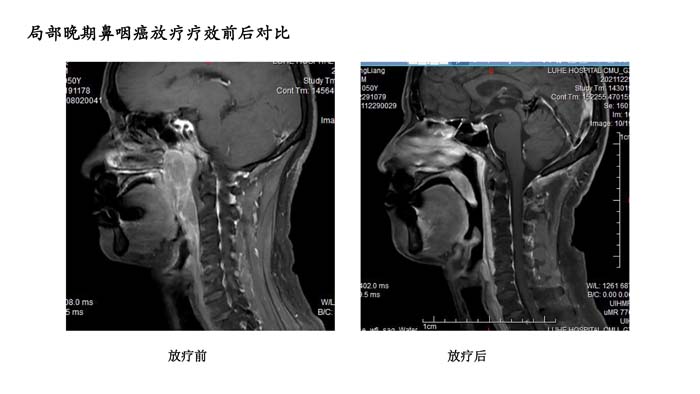

上一篇: 局部晚期鼻咽癌放疗疗效前后对比3